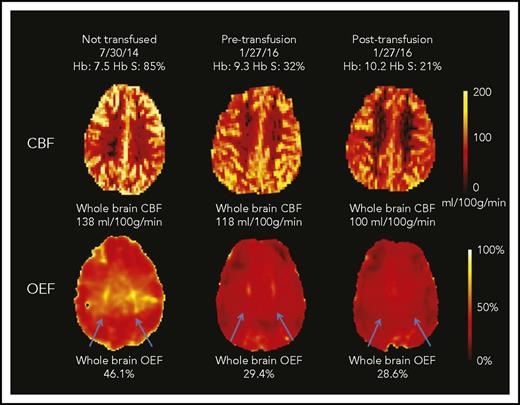

Transfusions decreased whole-brain CBF and OEF, without significant change in CMRO2 (Figure 1). Median CBF decreased from 88.0 (IQR, 73.4-110.8) to 82.4 mL/100 g per minute (IQR, 70.9-99.6; P = .005). Median OEF decreased from 34.4% (IQR, 32.1%-38.5%) to 31.2% (IQR, 29.6%-33.8%; P < .001; Table 2). Examples of CBF and OEF maps are shown in Figure 2. Although collectively both CBF and OEF decreased by an average of 9% posttransfusion, the change in CBF only moderately correlated with change in OEF within individuals (ρ = 0.48; P = .05), suggesting that CBF and OEF changes in response to transfusion effects may vary independently. Tissue-segmented (gray vs white matter) CBF, OEF, and CMRO2 demonstrated a similar response to transfusions as whole-brain values (Table 2).

CBF and OEF maps from a child with SCA. This 7-year-old boy underwent an MRI scan before CTT initiation and again before and after an exchange transfusion (only CTT values included in cohort-level analyses). The whole-brain CBF was highest at his first scan (138 mL/100 g per minute). After 17 months of CTT, his pretransfusion CBF was lower than his initial scan (118 mL/100 g per minute; 14% drop) and further decreased after transfusion to 100 mL/100 g per minute (15% drop). The whole-brain OEF was highest at the first scan (46.1%), with dramatic reduction in OEF measured pretransfusion (29.4%; 38% drop) and only modest reduction posttransfusion (28.6%; 3% drop). His OEF maps were also notable for regionally elevated OEF in the deep white matter (blue arrows), which was most prominent before CTT initiation. This peak OEF was still detectable on the pretransfusion scan, although less prominent. After transfusion, the peak OEF region was absent, with restoration of homogeneous OEF across the brain.

Transfusions reduce regions of peak OEF in deep white matter